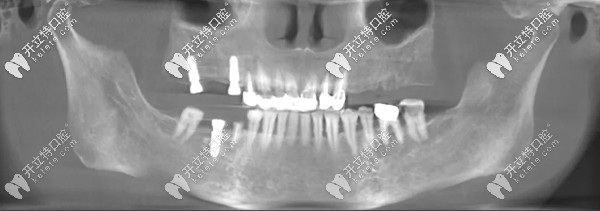

王阿姨種牙前

▲王阿姨種牙前牙片